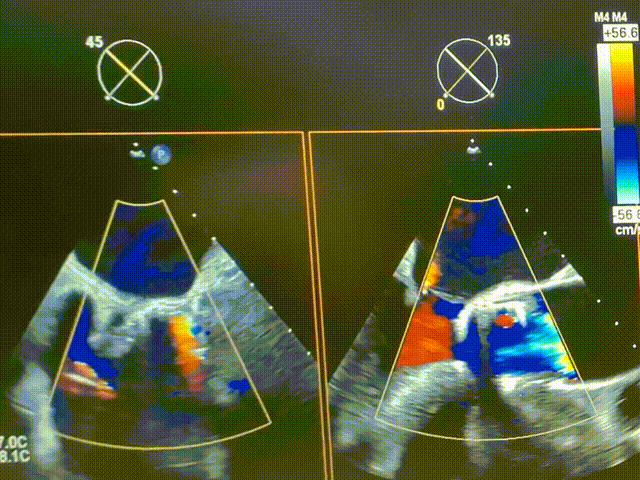

术前超声

术后超声